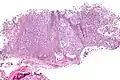

Micrograph of a myoepithelioma. H&E stain. | |

The myoepithelial cells may be spindled, plasmacytoid, eithelioid or clear. Tubules or epithelium are absent, or present in a small amount (<5%) by definition. Tumours with myoepithelial cells and a large amount of tubules are classified as pleomorphic adenomas (which must also contain the characteristic chondromyxoid stroma, which is normally absent in myoepithelioma).